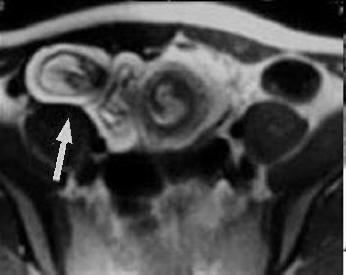

| Aspect IRM d'une diverticule

de D2 ( coupe axiale ) . Image hydro-aerique a

droite sous hepatique |